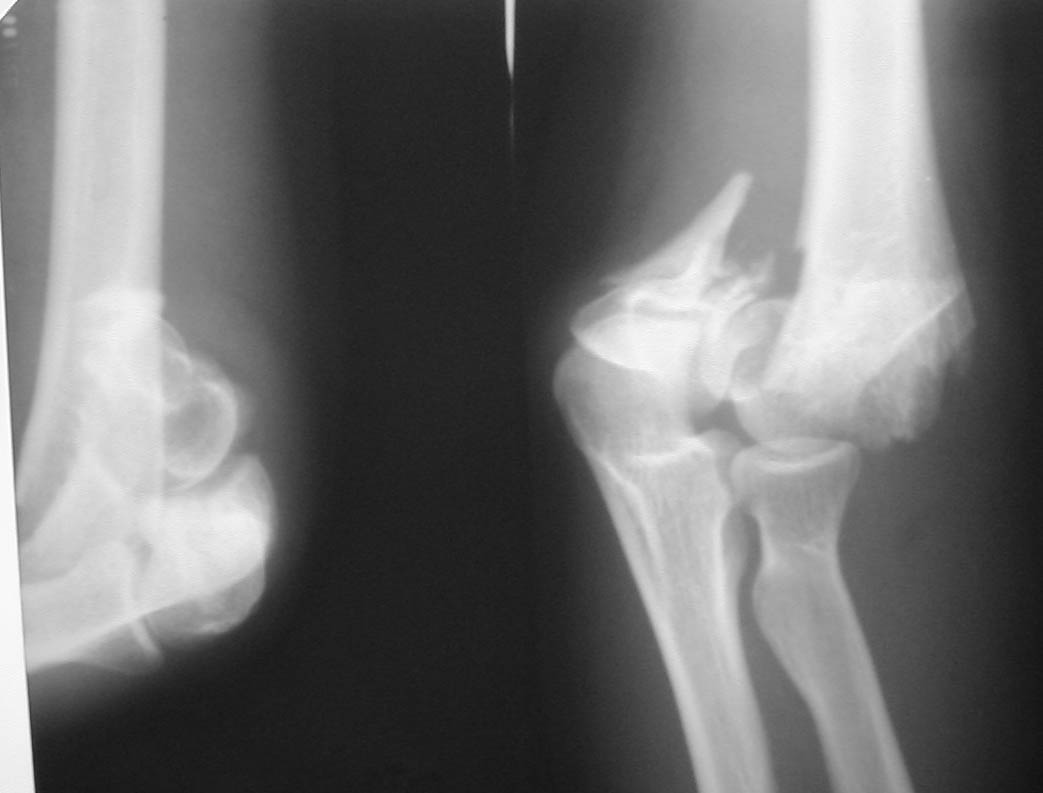

Женщина, 37 лет. Травма в результате падения на улице. Закрытый многооскольчатый перелом дистального метаэпифиза левой плечевой кости со смещением. Неврологических и сосудистых нарушений не выявлено.Лечение? Если внешняя фиксация, то - каков монтаж АВФ? Сейчас пациентка на скелетном вытяжении.С уважением,А.В.Владзимирский

• Кликните для загрузки файла k1.JPG

39KB (40781 bytes)